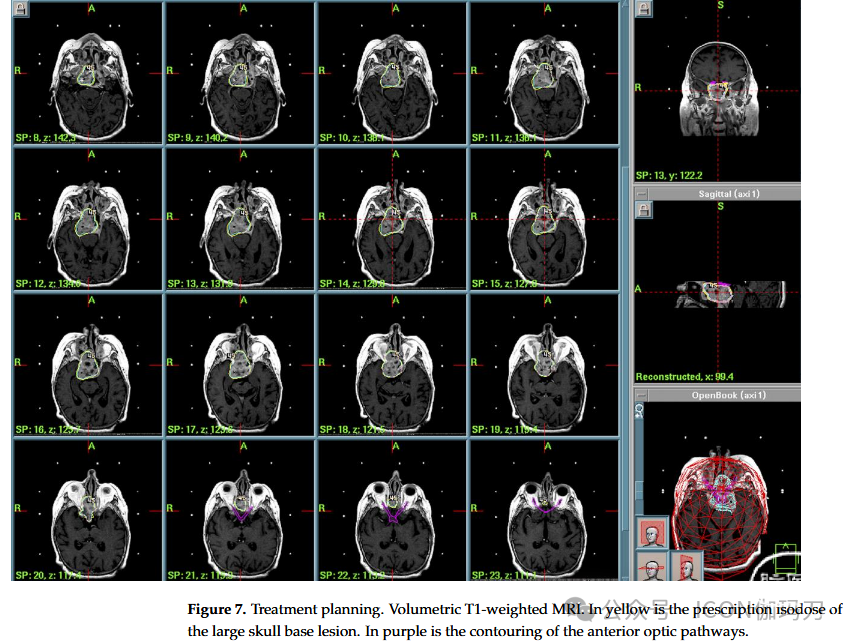

病例7:一名70岁女性,最近出现左眼上睑下垂,视野缺损,复视,额部头痛。MRI显示大量扩张性病变侵袭蝶窦,伴有斜坡和筛窦糜烂。患者在另一中心接受神经外科手术,组织学检查显示为砂砾性骨化纤维瘤(psammomatoid ossifying fibroma)。术后MRI显示蝶窦及斜坡周围残留病变。辅助放疗总剂量为59 Gy,分30次进行。术后6个月的MRI显示,斜坡周围残留肿瘤持续存在,并延伸至蝶鞍底,即筛窦的后部。尽管先前的手术和放疗,仍然存在残余肿瘤。由于解剖复杂性和先前的辐射暴露,GKRS被一个多学科团队选择来优化局部控制。2004年进行治疗(PI为50%,PD为11 Gy, MD为22 Gy)。术后过程顺利,患者出院回家。患者于2016年去世,享年83岁(GKRS治疗后12年);死亡原因与骨化性纤维瘤无关。(图7)。

图7。治疗计划。体积T1加权MRI。黄色是大颅底病变的处方等剂量。紫色是前部视神经的轮廓。